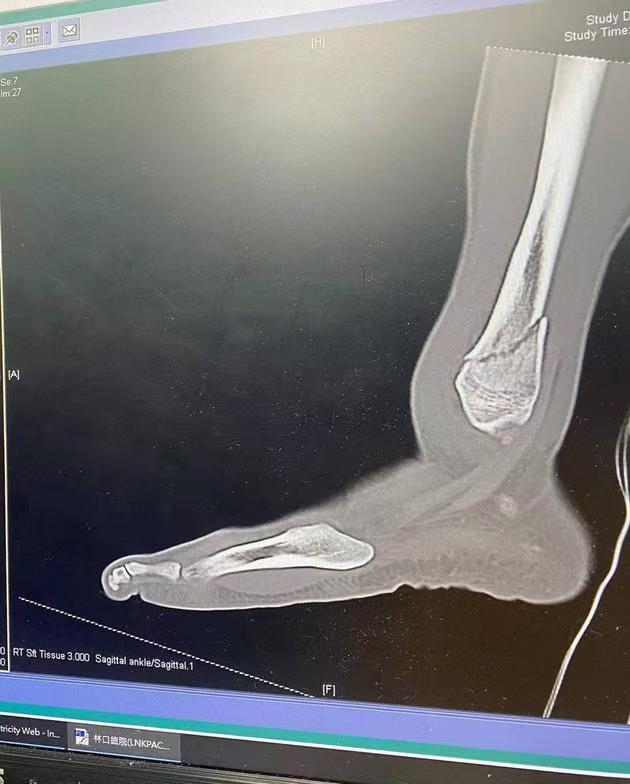

踝关节骨折:年轻人好动,参加体育活动时,在跳跃、奔跑、扭转过程中,容易造成踝关节周围骨折。此外,老年人因骨质疏松,也较容易发生踝关节骨折。